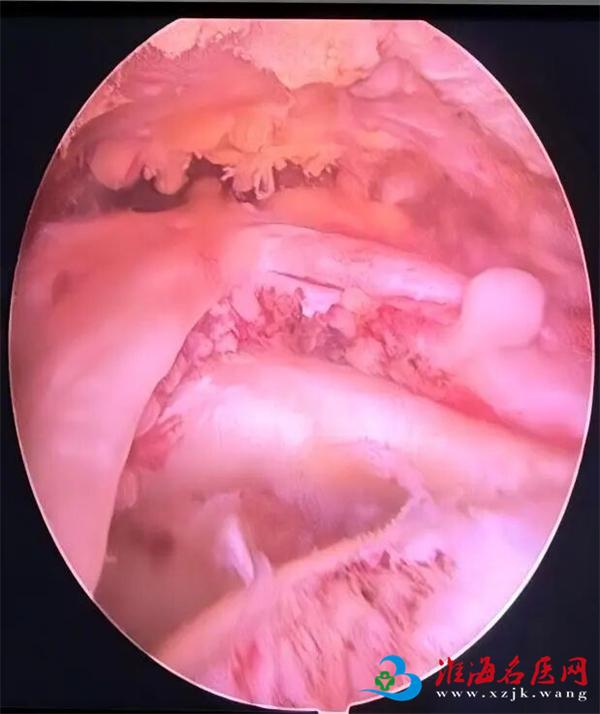

关节镜下肩袖修补术

以往,治疗肩袖损伤往往需要大面积切开肩膀进行开放手术,这不仅创伤大、恢复慢,还可能留下明显的疤痕。如今,随着医疗技术的进步,关节镜下肩袖修补术已成为主流和首选方法。这项技术仅需在肩部开3-4个如“钥匙孔”般微小的切口(约1厘米),然后伸入高清微型摄像头(关节镜)和精密手术器械,医生通过监视器放大清晰的影像进行操作,精准地对撕裂的肌腱进行修复和固定。

视野清晰,处理精准。 高清镜头可将关节内结构放大数十倍,使手术视野更清晰,能发现X光、MRI难以显示的隐匿损伤,并进行精准修复。

一次手术,全面诊断。 关节镜技术在修补肩袖的同时,还能全面检查并处理肩关节内的其他并存问题,如肩峰成形、清理增生滑膜等。